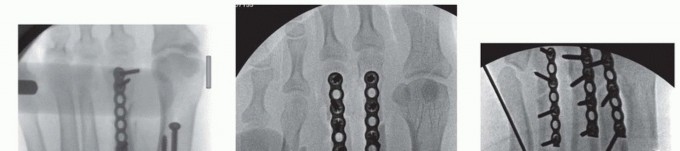

1. ## Closure

The wounds are irrigated, and closure commences with the medial incision. The floor of the EHL tendon sheath (and subperiosteal flaps) is closed with deep no. 0 absorbable suture, thereby sealing the intra-articular surfaces of the first and second tarsometatarsal joints and intercuneiform joints.

The EHL tendon sheath is closed in similar fashion, thereby sealing the tendon (

TECH FIG 6A

).

The remainder of the incision is closed in layered fashion with subcutaneous 2-0 absorbable suture and 3-0 monofilament suture for the skin layer using the modified Allgöwer-Donati technique (

TECH FIG 6B

The tourniquet is deflated and sterile dressings are placed, followed by a bulky Jones dressing and Weber splint. TECH FIG 6 • Wound closure. A. Deep layered closure sealing intra-articular contents and EHL tendon. B. Skin closure with modified Allgöwer-Donati technique.